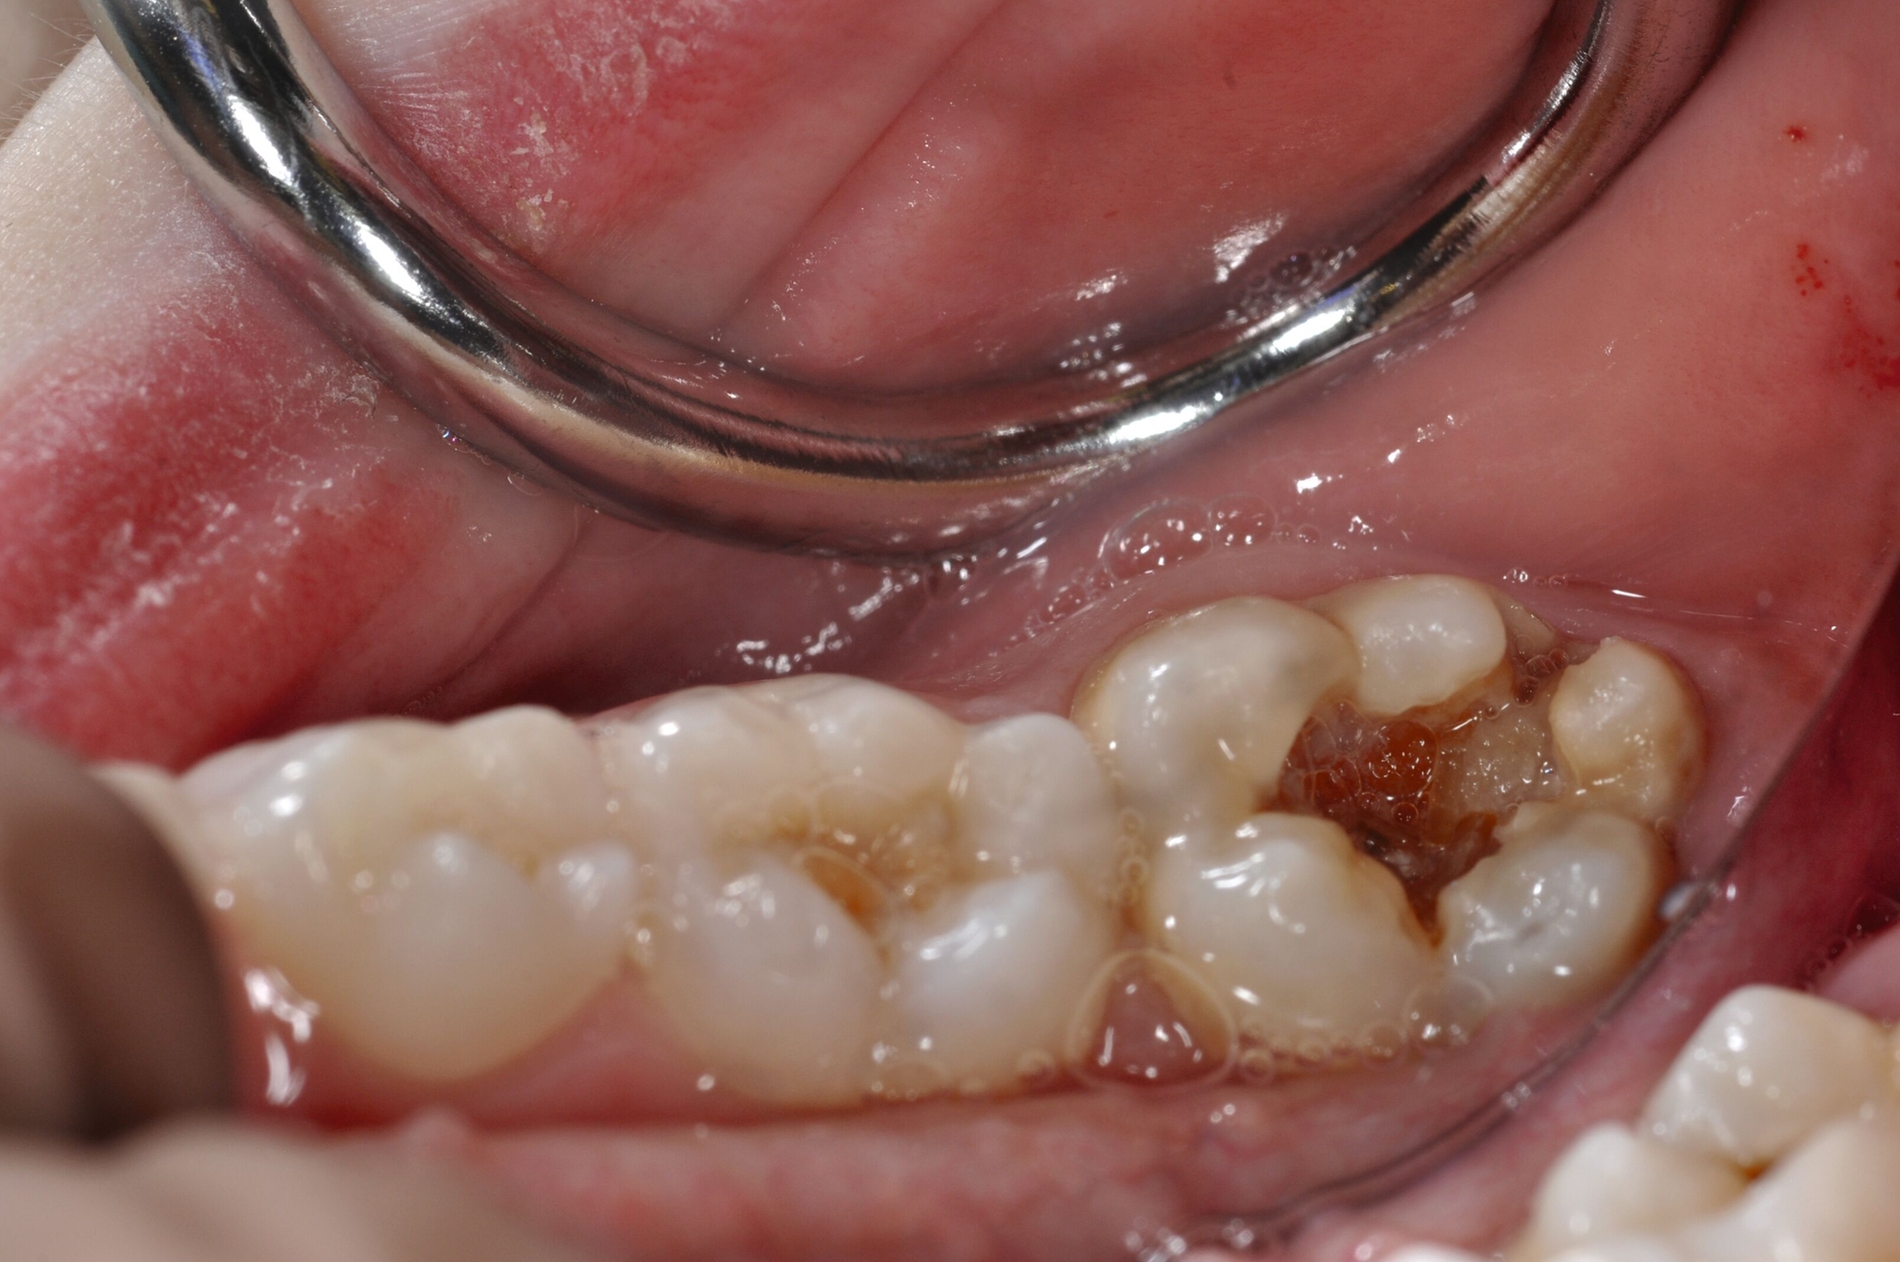

Diese Klassifikation dient als Grundlage für die Therapieempfehlungen. Deutlich wird, dass aufgrund der Symptomatik die Therapie der Zähne höchst unterschiedlich ausfällt. Dass etwa eine Opazität ohne Überempfindlichkeit (Index 1, Abbildung 1) ein anderes therapeutisches Vorgehen erfordert als ein Zahn mit nahezu komplettem Einbruch der Zahnoberfläche und mit Hypersensitivität (Index 4, Abbildung 2), ist offensichtlich.

Die temporäre Therapie C (kurzfristig)

Die Therapie C hat das Ziel, MIH-Zähne vorübergehend zu versorgen, bis der vollständige Durchbruch der Zähne eine adhäsive Restauration ermöglicht, um die hypersensiblen Zähne zu desensibilisieren oder/und die Mitarbeit für die weitere Behandlung aufzubauen. Vor dem Hintergrund des erhöhten Kariesrisikos dieser Zähne (Abbildung 2) muss durch die Maßnahmen eine Kariesprogression vermieden werden.

Als mögliche Maßnahme steht eine Abdeckung der Defekte mittels konventioneller Glasionomerzemente (GIZ) zur Verfügung. Vorteil der Materialien ist die schnelle und einfache Applikation der Zemente. Bei MIH-Molaren werden diese in der Regel mittels der sogenannten ART-Technik (Atraumatic Restorative Treatment) eingesetzt [Grossi et al., 2018]. Dabei wird lediglich mit einem Handinstrument die Zahnoberfläche gereinigt und gegebenenfalls Karies exkaviert. Anschließend wird die Kavität unter relativer Trockenlegung mit dem GIZ aufgefüllt.

Der Vorteil der Methode ist, dass die betroffenen Zähne auch ohne Lokalanästhesie und Präparation versorgt werden können. Die temporäre Versorgung ermöglicht es, die Patienten an die zahnärztliche Behandlung zu gewöhnen. Häufig führt diese temporäre Versorgung auch zu einer Reduktion der Hypersensitivität der MIH-Zähne. Nachteil der GIZ-Versorgung ist das Risiko einer Füllungsfraktur oder eines vollständigen Verlusts der Füllung (Abbildung 4). Aktuelle Erhebungen bestätigen eine Erfolgsrate von über 80 Prozent nach einem bis zwei Jahren [Durmus et al., 2021; Mahfouz et al., 2025].

Der Behandlungsfall (Abbildung 4d) veranschaulicht die Schwächen des Verfahrens. Wird das Angebot der regelmäßigen Kontrollen nicht wahrgenommen, so droht bei Verlust der Füllung die Kariesprogression. In dem vorliegenden Fall konnte jedoch eine endodontische Maßnahme vermieden und durch die selektive Kariesentfernung die Zahnhartsubstanz weitestgehend erhalten werden.